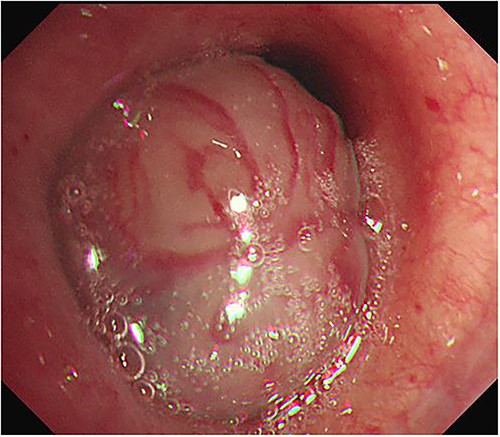

A 76-year-old female patient presented to the hospital with dyspnea and coughing. A chest X-ray (Fig. 1a) revealed a possible tumor in the left main bronchus and atelectasis of the left lower lobe. A chest computed tomography scan confirmed an endobronchial tumor obstructing the left lower lobe bronchus that had grown toward the main bronchus to the point of near complete obstruction. A malignant tumor in the endobronchial region was suspected (Fig. 1b and c). Bronchoscopy was performed and revealed an endobronchial tumor with a smooth surface that obstructed most of the left main bronchus (Fig. 2). Blood vessels were visible on the tumor surface. The tumor did not appear amenable to endobronchial treatment or resection. The results of bronchoscopy suggested a benign tumor, although malignant disease could not be ruled out. Surgery was chosen for treatment.

Bronchoscopy was performed and revealed an endobronchial tumor with a smooth surface that was obstructing most of the left main bronchus.